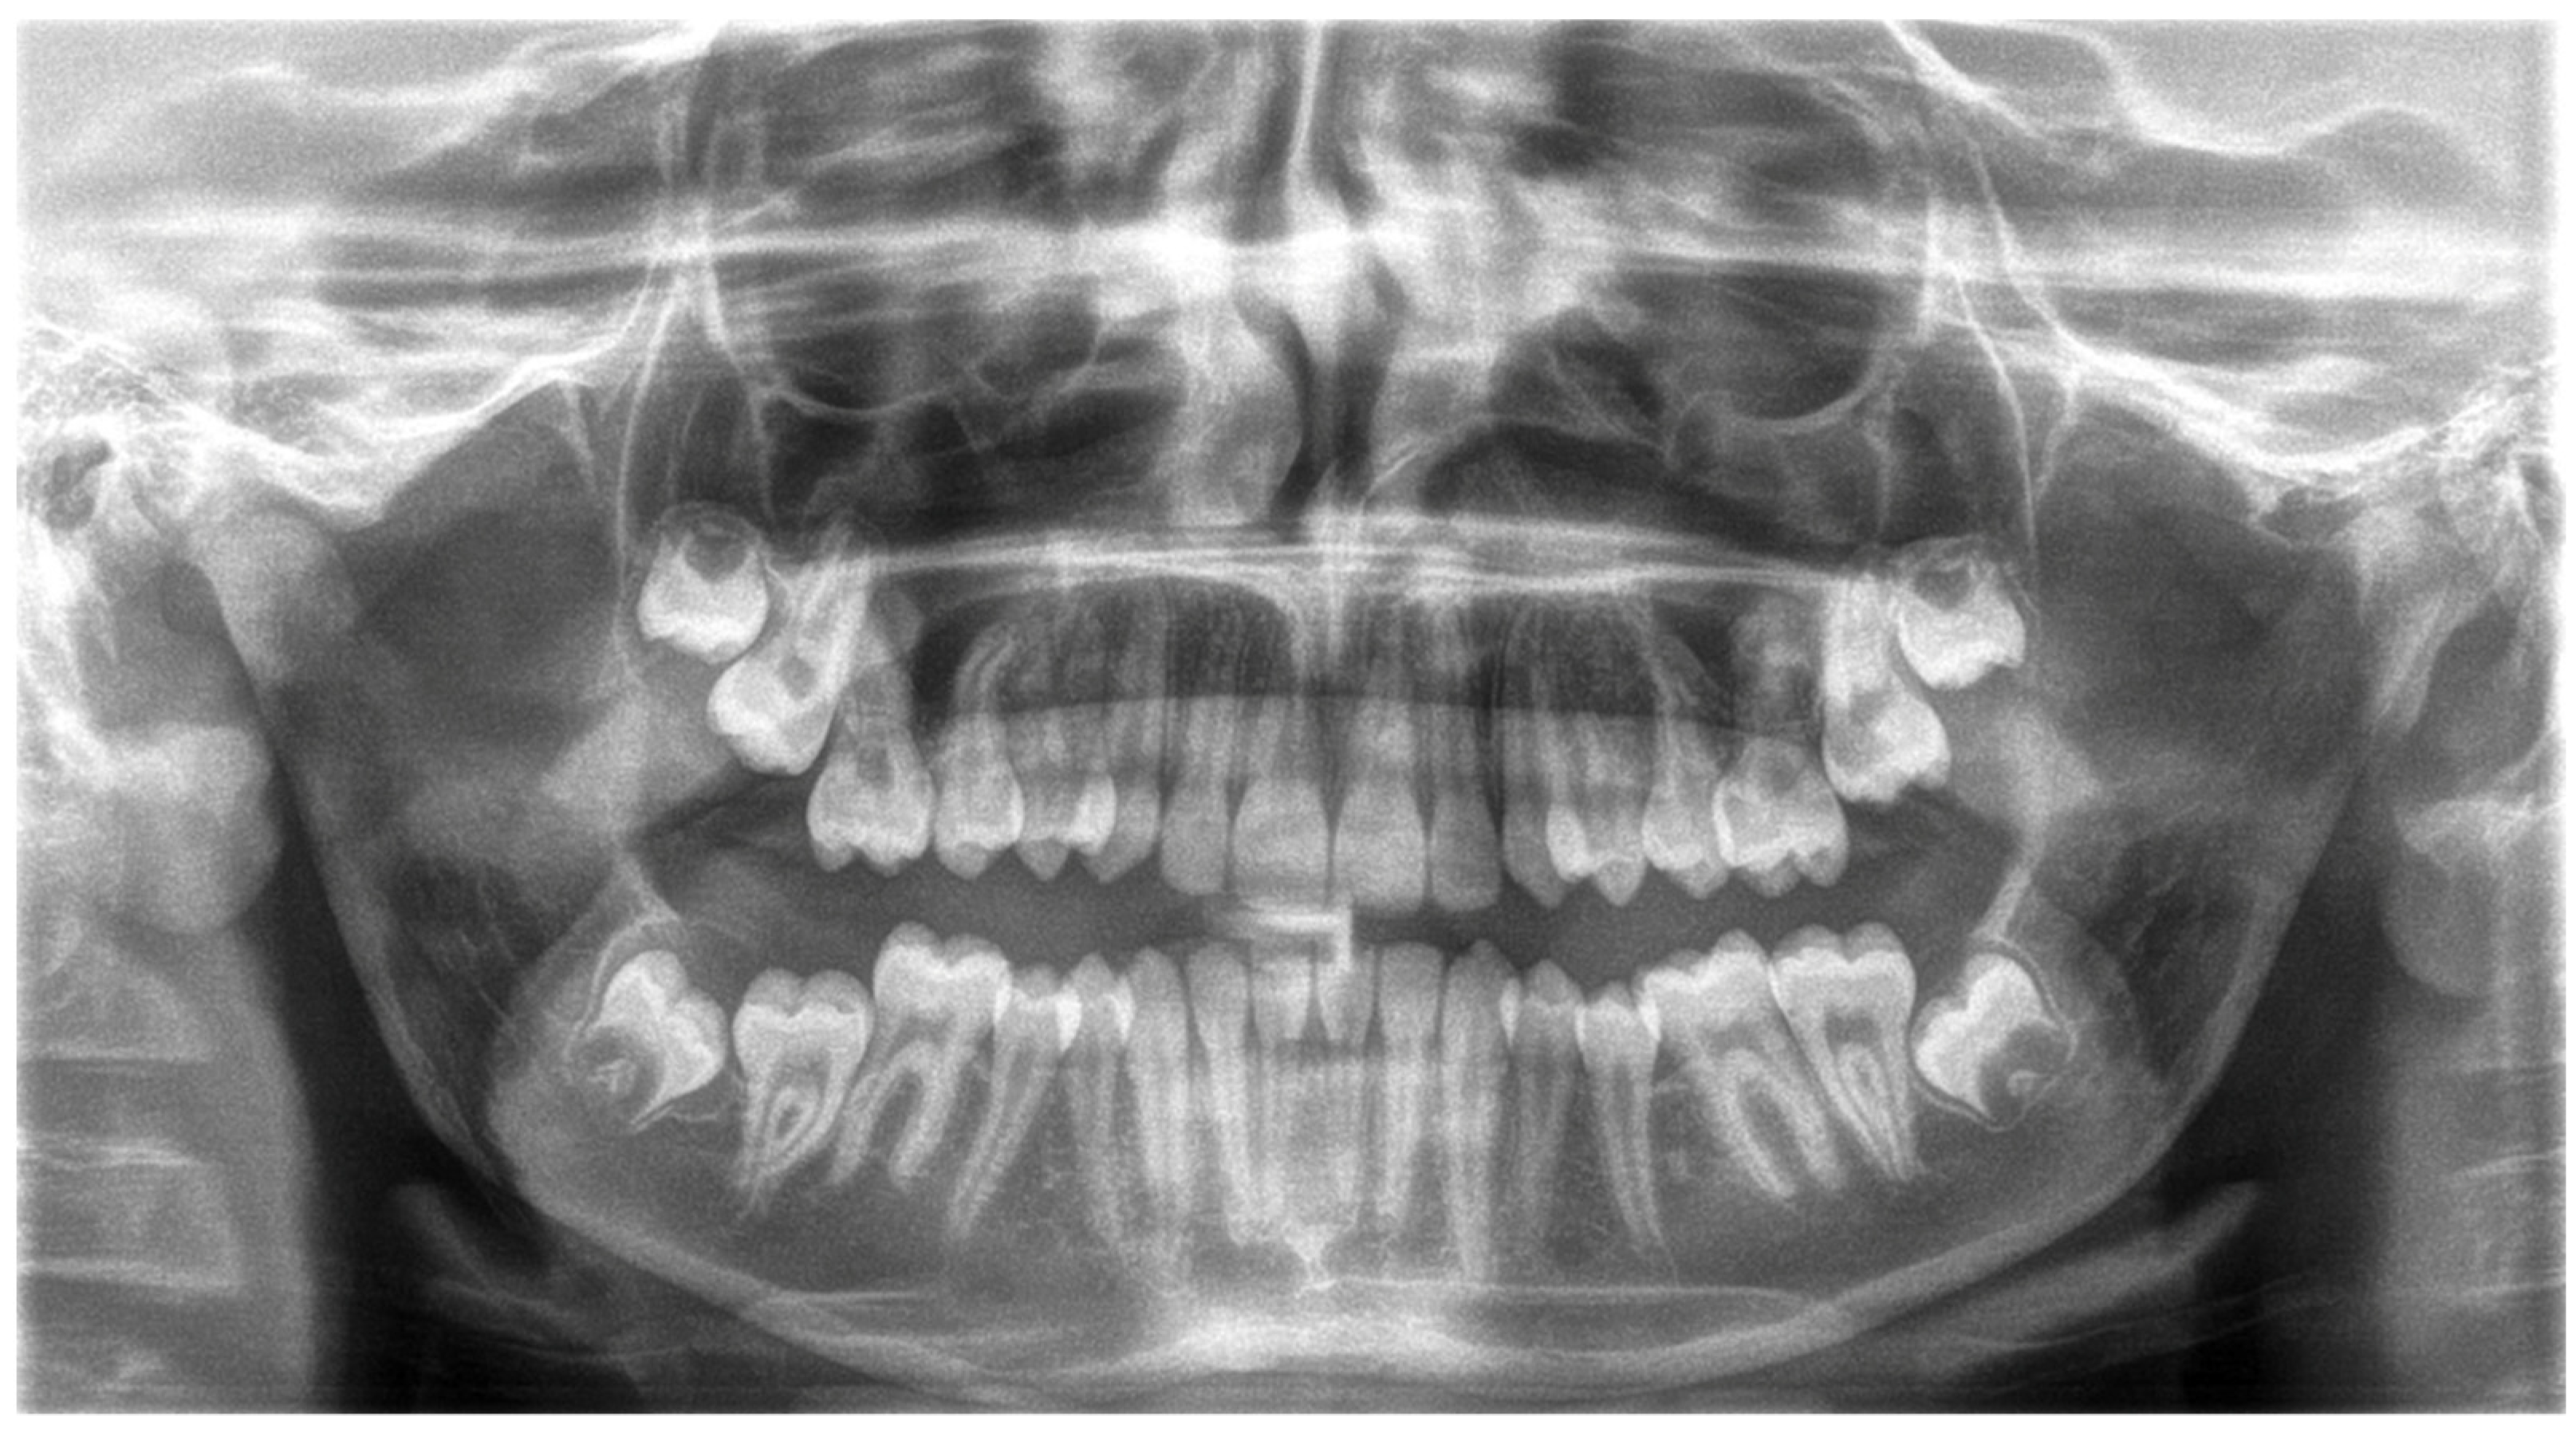

| Description | Cephalometric Measurements | Value | Mean | SD |

|---|---|---|---|---|

| Maxilla to Cranial Base | SNA | 78.67 | 82.00 | 3.00 |

| NL-NSL | 11.29 | 8.00 | 4.00 | |

| Mandible to Cranial Base | SNB | 79.03 | 80.00 | 3.00 |

| ML-NSL | 25.82 | 28.00 | 5.00 | |

| Maxilla to Mandible | ANB | −0.36 | 3.00 | 2.50 |

| WITS [mm] | −2.40 | 0.00 | 2.00 | |

| ML-NL | 14.53 | 20.00 | 7.00 | |

| Maxillary Dentition | U1-NA [mm] | 1.50 | 3.70 | 2.00 |

| U1-NA | 16.32 | 21.00 | 4.00 | |

| Mandibulary Dentition | L1-NB [mm] | −1.98 | 3.80 | 5.00 |

| L1-NB | 2.44 | 24.00 | 4.00 | |

| Soft Tissue | Nasio-labial angle | 89.72 | 110.00 | 7.00 |

| SNPg | 81.49 | 81.00 | 3.00 | |

| N-S-Ba angle | 138.49 | 132.00 | 4.00 | |

| Gn-tgo-Ar angle | 133.52 | 122.00 | 7.00 | |

| NB-H angle | 6.09 | 9.00 | 3.00 | |

| U1-L1 | 161.60 | 133.00 | 8.00 | |

| Pg-NB [mm] | 4.91 | 2.30 | 2.00 | |

| N-Sp’/Sp’-Gn [%] | 88.21 | 80.00 | 7.00 |